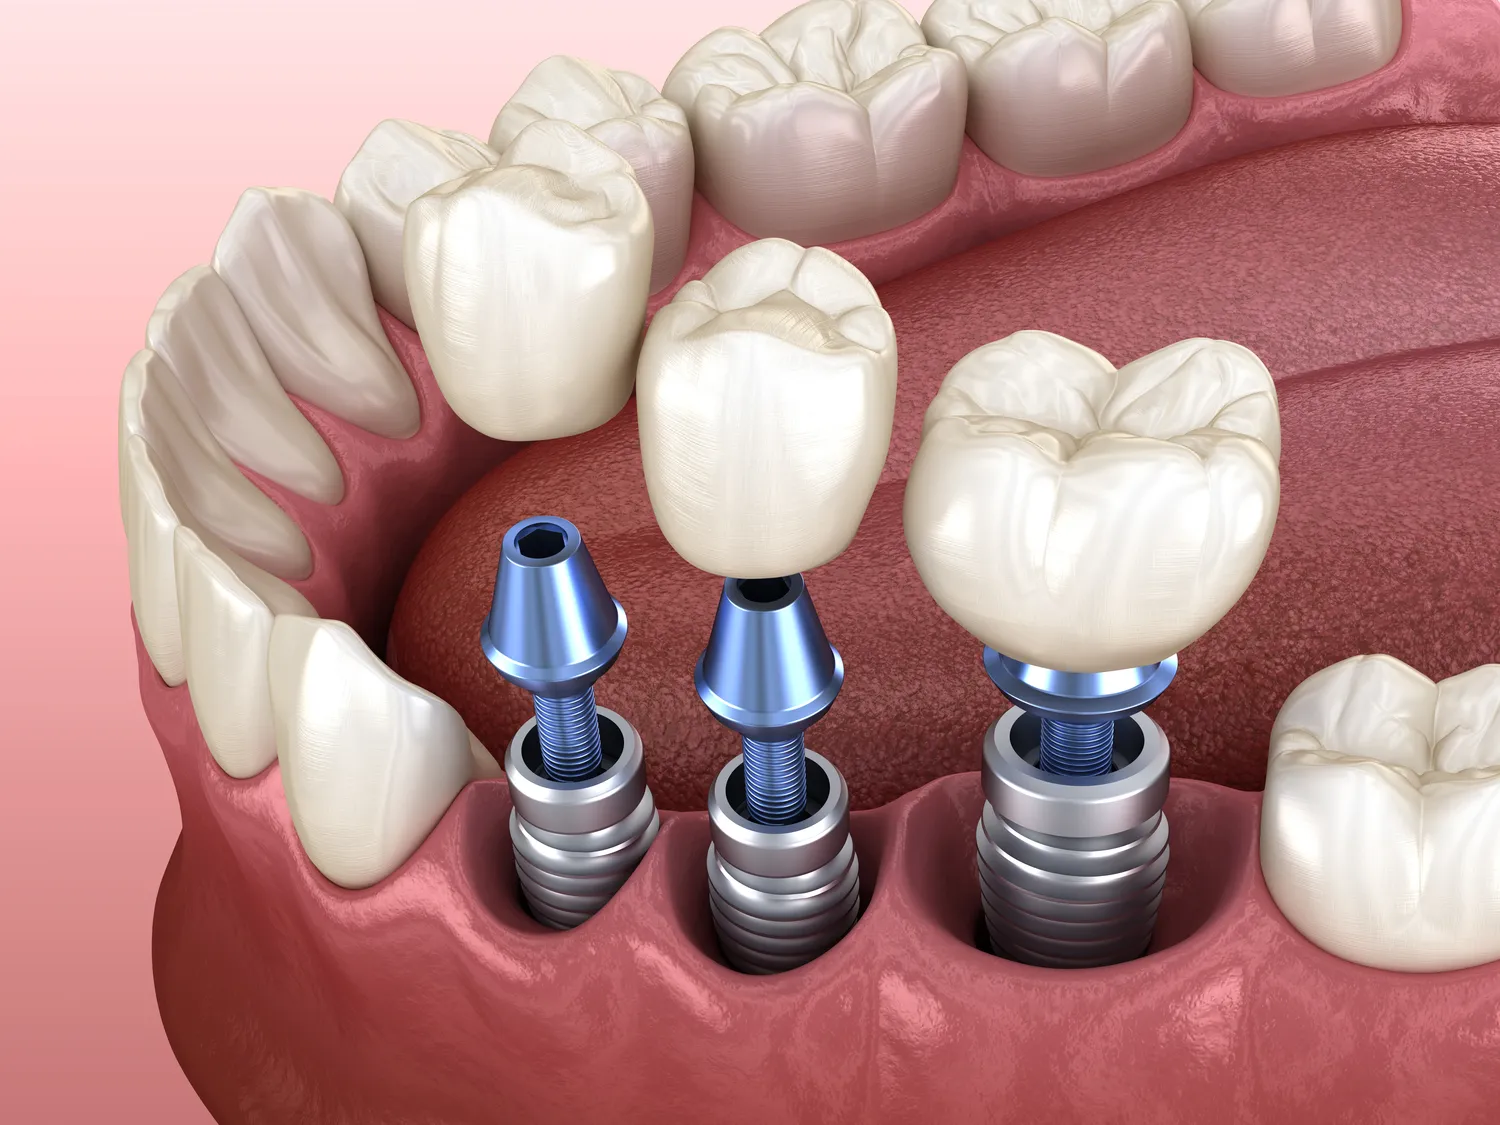

Implanty zębowe to popularne rozwiązanie dla osób, które straciły zęby i pragną przywrócić sobie pełną funkcjonalność jamy ustnej. Koszt implantów zębowych różni się znacznie w zależności od kraju, w którym są wykonywane. W krajach zachodnich, takich jak Stany Zjednoczone czy Niemcy, ceny mogą wynosić od kilku tysięcy do nawet dziesięciu tysięcy dolarów za jeden implant, co często obejmuje również dodatkowe procedury, takie jak zdjęcia rentgenowskie czy konsultacje. W Europie Środkowej i Wschodniej, na przykład w Polsce czy Czechach, ceny są znacznie niższe i mogą wynosić od dwóch do pięciu tysięcy złotych za implant. Warto jednak pamiętać, że niższa cena nie zawsze oznacza gorszą jakość, a wiele klinik w tych krajach oferuje usługi na wysokim poziomie. Dodatkowo, koszty mogą być różne w zależności od używanych materiałów oraz technologii.

Cena implantów zębowych jest uzależniona od wielu czynników, które warto rozważyć przed podjęciem decyzji o leczeniu. Po pierwsze, lokalizacja kliniki ma kluczowe znaczenie. W dużych miastach ceny mogą być wyższe ze względu na większe koszty utrzymania gabinetu oraz wyższe zarobki specjalistów. Po drugie, doświadczenie stomatologa również wpływa na koszt zabiegu. Lekarze z długim stażem i licznymi certyfikatami mogą pobierać wyższe stawki za swoje usługi. Kolejnym czynnikiem jest rodzaj implantu oraz materiał, z którego jest wykonany. Implanty tytanowe są najczęściej stosowane i uznawane za najbardziej trwałe, ale ich cena może być wyższa niż w przypadku implantów ceramicznych czy kompozytowych. Dodatkowo, konieczność przeprowadzenia wcześniejszych zabiegów przygotowawczych, takich jak augmentacja kości czy leczenie chorób przyzębia, także zwiększa całkowity koszt leczenia.

W ostatnich latach rozwój technologii w dziedzinie implantologii stomatologicznej znacząco wpłynął na sposób, w jaki przeprowadzane są zabiegi. Jednym z najważniejszych osiągnięć jest zastosowanie cyfrowego planowania zabiegów, które umożliwia precyzyjne zaplanowanie umiejscowienia implantu jeszcze przed rozpoczęciem procedury. Dzięki temu lekarze mogą lepiej ocenić warunki anatomiczne pacjenta oraz dostosować technikę wszczepienia implantu do indywidualnych potrzeb. Kolejnym innowacyjnym rozwiązaniem jest wykorzystanie technologii CAD/CAM do produkcji implantów i koron protetycznych. Dzięki tej technologii możliwe jest uzyskanie wysokiej precyzji wykonania oraz szybsze dostarczenie gotowych elementów do pacjenta. Również zastosowanie materiałów biokompatybilnych, takich jak tytan czy ceramika, przyczynia się do zwiększenia trwałości i estetyki implantów. Warto również wspomnieć o mini-implantach, które są mniejsze od tradycyjnych i mogą być stosowane w mniej inwazyjny sposób, co skraca czas rekonwalescencji pacjenta.

Rehabilitacja po wszczepieniu implantu zębowego to istotny element całego procesu leczenia, który ma na celu przywrócenie pełnej funkcjonalności jamy ustnej oraz estetyki uśmiechu. Czas rehabilitacji różni się w zależności od indywidualnych predyspozycji pacjenta oraz rodzaju zastosowanego implantu. Zazwyczaj proces gojenia trwa od trzech do sześciu miesięcy; w tym czasie implant integruje się z kością szczęki poprzez proces zwany osteointegracją. Po zakończeniu tego etapu można przystąpić do mocowania korony protetycznej na implancie. Warto jednak pamiętać, że rehabilitacja nie kończy się wraz z umocowaniem korony; pacjent powinien kontynuować regularne wizyty kontrolne u stomatologa oraz dbać o higienę jamy ustnej przez całe życie. Odpowiednia pielęgnacja implantów oraz regularne kontrole pozwolą uniknąć ewentualnych komplikacji zdrowotnych i zapewnią długotrwałe efekty leczenia.